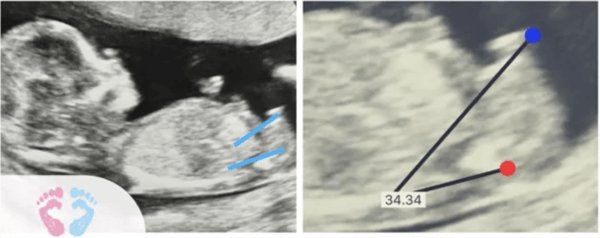

In order to be able to make a gender prediction the ultrasound in nub theory must display a profile view of the baby, and the nub must be visible, this can be a challenge because babies move and good profile views are hard to get. If you do achieve this image, here are the steps for nub method:

- Find the spine: The angle of the spine serves as a baseline to compare with the angle on the nub, which is our next step.

- Find the nub: It should be a defined white line along where the legs of the baby should be.

- Find the angle: Comparing the direction of the spine with nub, see if the angle is more or less than 30 degrees.

Through nub theory, the angle of the genital tubercle is used to determine a baby’s gender. Generally, if the nub is above 30 degrees, the baby is likely a boy.

Conversely, when the angle is 10 degrees or less, it usually means that the baby is a girl. If the angle is between 11 and 29 degrees, this would be termed as ‘ambiguous genitalia’ or ‘unknown sex,’ and you would need your doctor to interpret it for more accuracy.